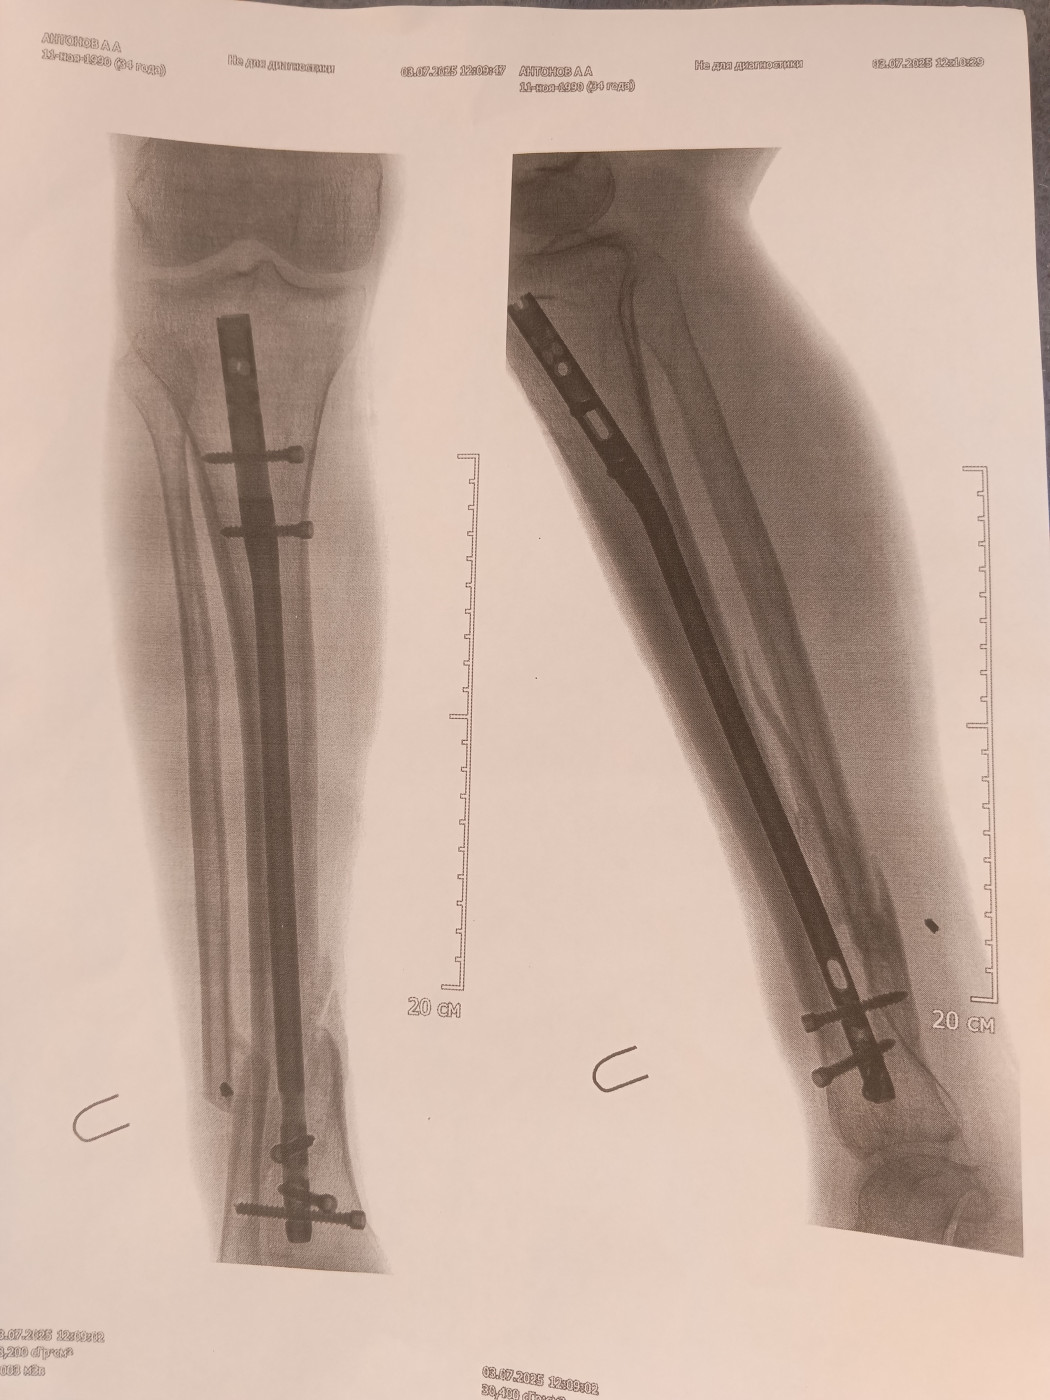

Когда можно начинать ходить после остеосинтеза костей голени?Здравствуйте. Хронических заболеваний нет, 40 лет. Диагноз — Закрытый перелом с-н/3, заднего края большеберцовой кости, подсиндесмозный перелом малоберцовой кости слева со смещением отломков. 30.05. 2025 проведена операция Закрытая репозиция, остеосинтез большеберцовой кости слева интрамедуллярным блокируемым штифтом, открытая репозиция остеосинтез малоберцовой кости слева пластиной, заднего края большеберцовой кости винтами. В шесть недель после операции сделала контрольный рентген ( снимков нет) Интерпретация результатов |

Здравствуйте. Консолидация на настоящее время не произошла. Нагрузку на ногу давать не следует. Для полноценной интерпретации результатов обследования необходимо иметь всю информацию, в том числе данные анамнеза, жалобы, клиническую картину, данные других анализов и обследований. Необходимо посетить травматолога с результатами. По совокупности данных будет определена тактика и даны рекомендации |